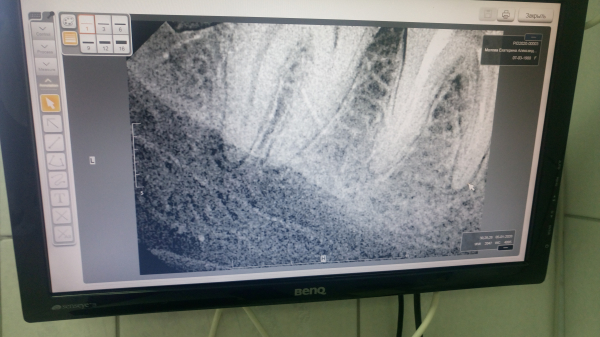

Без клинического осмотра сложно определить однозначно причину. Похоже, в области пролеченного зуба имеется периапикальное воспаление. В области дистального корня соседнего зуба, также определяется разрежение костной ткани. Исходя из снимка, сложно судить, так как возможно наличие артефактов. Причиной онемения может быть воспалительный процесс в области нервных окончаний.